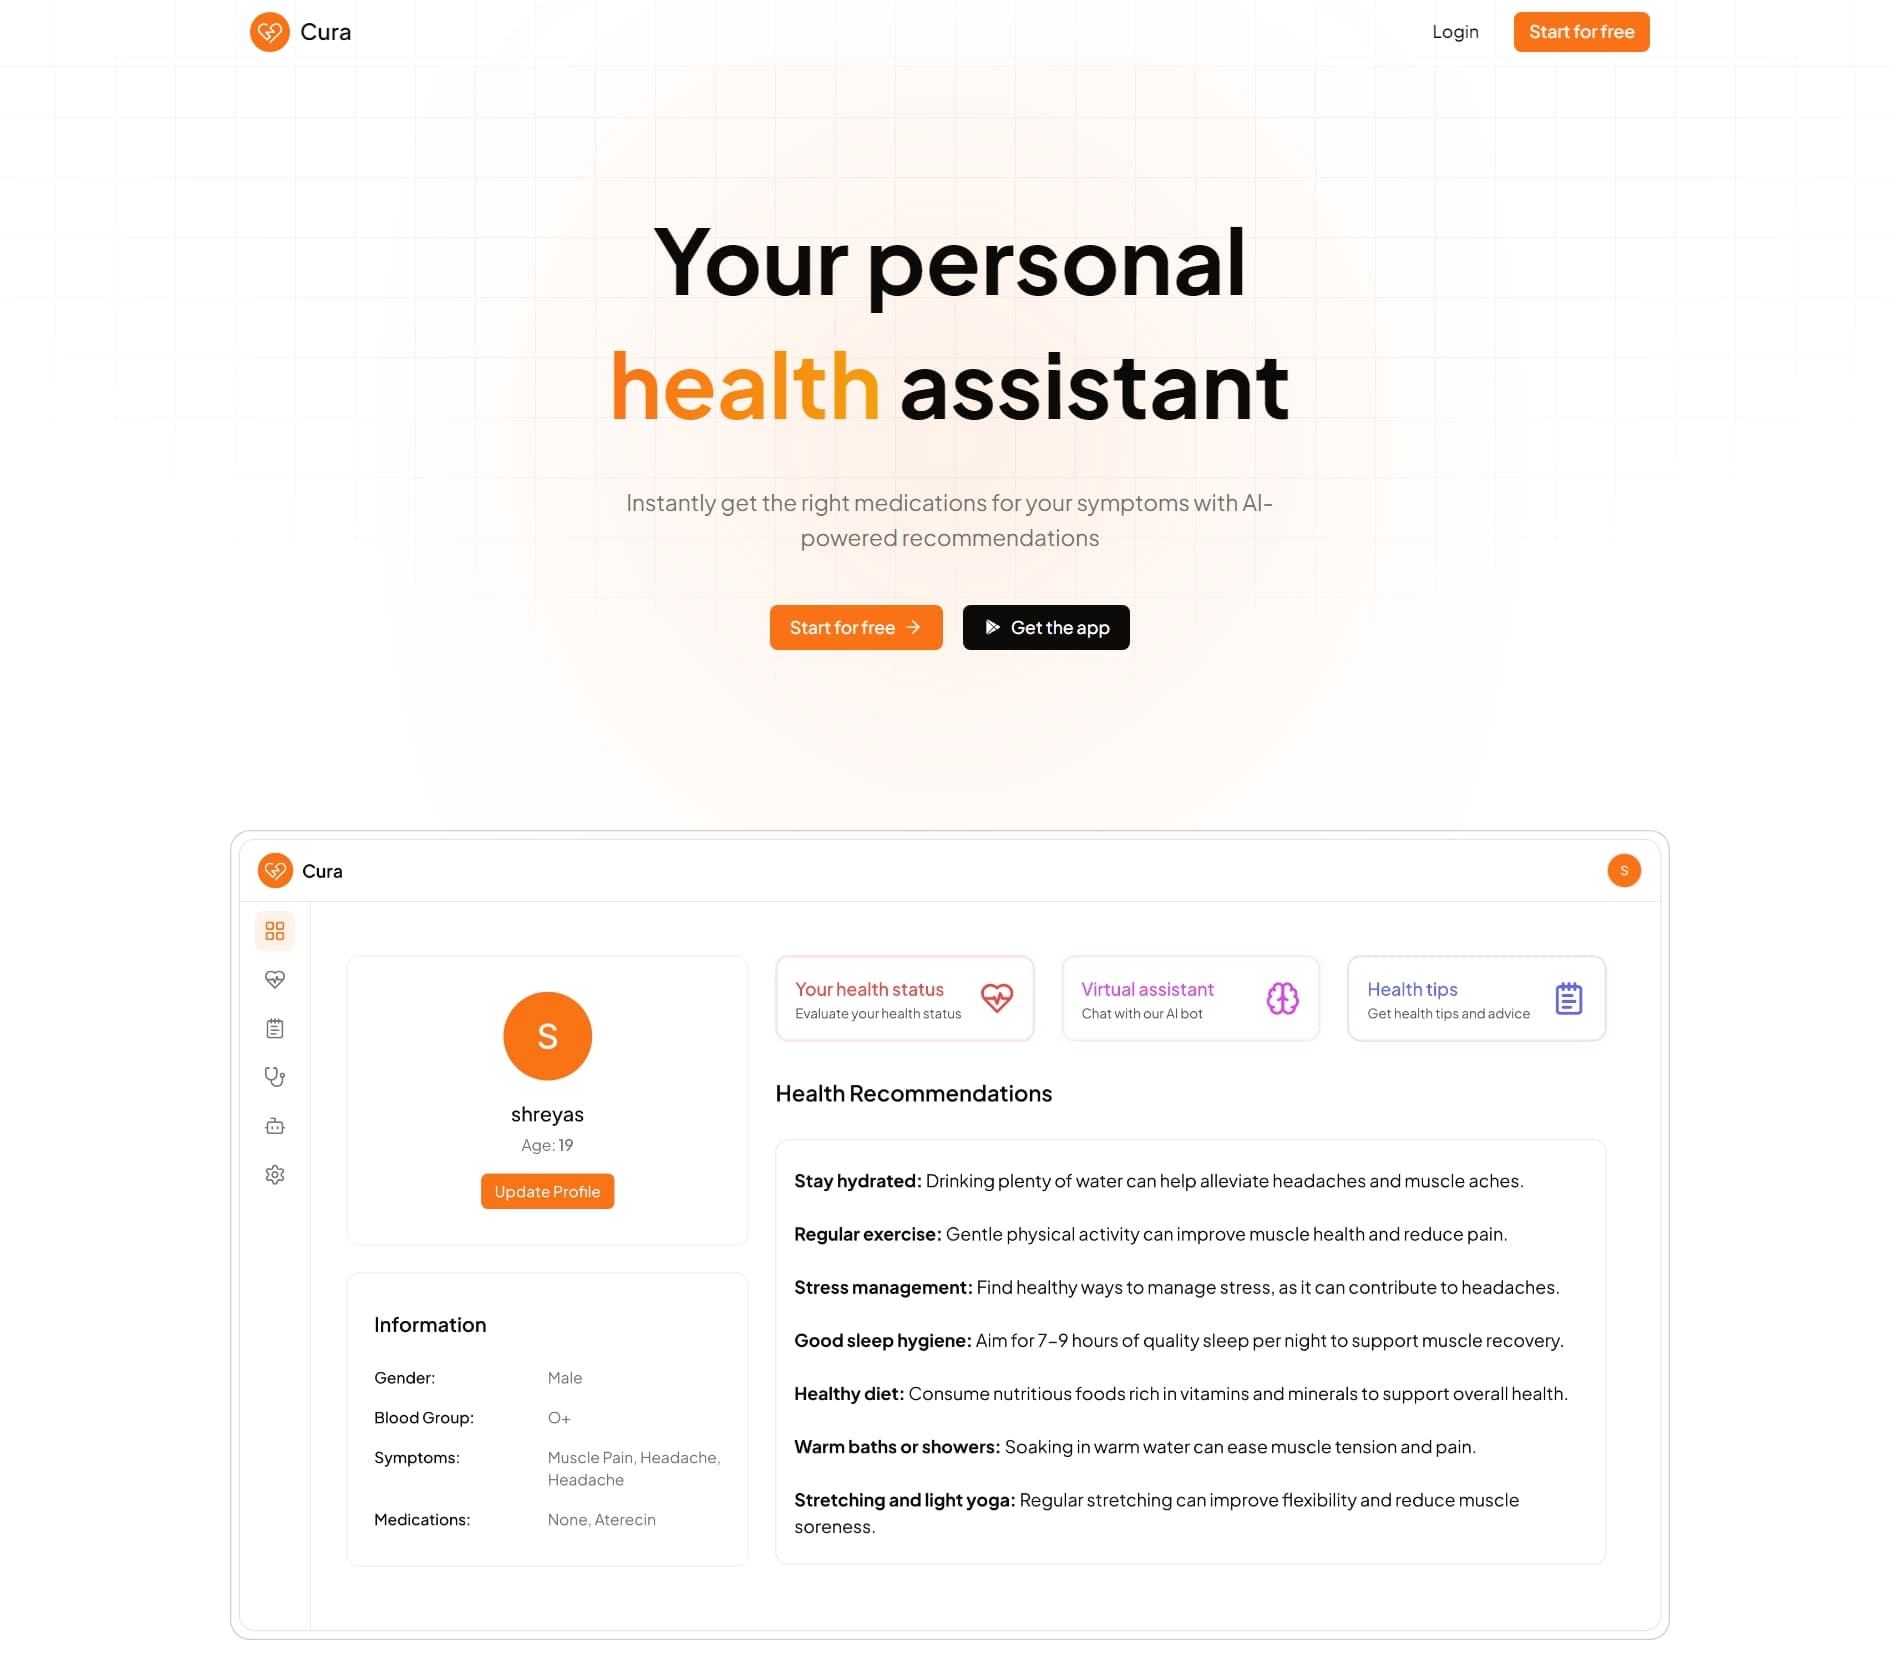

Cura Med

A comprehensive virtual health coach platform that leverages AI to provide personalized health and wellness recommendations.0